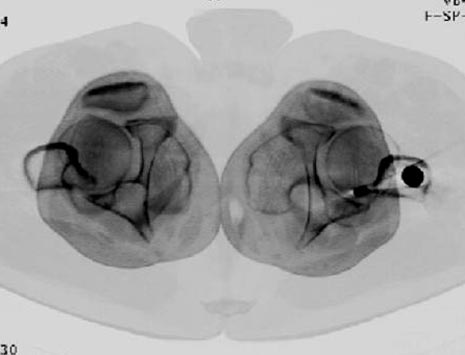

Снимки представлены: 1 мес; 3 мес; 1 год; 2 года, предоперационные и ротационная КТ грамма

Ротационно 22 градусов внутренная

Смещение диафиза по поперечнику 75%